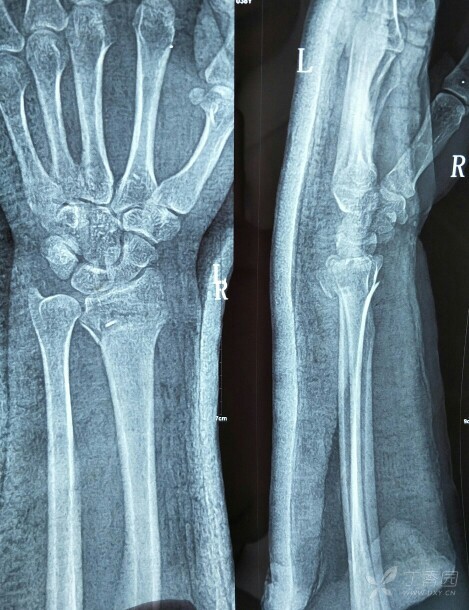

一个右科雷氏骨折的治疗